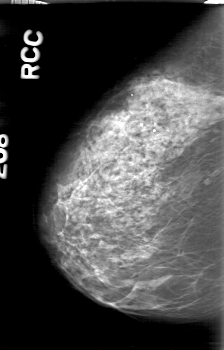

D_4164_1.RIGHT_CC

RIGHT_CC LINES 5236 PIXELS_PER_LINE 3346 BITS_PER_PIXEL 12 RESOLUTION 43.5 NON_OVERLAY